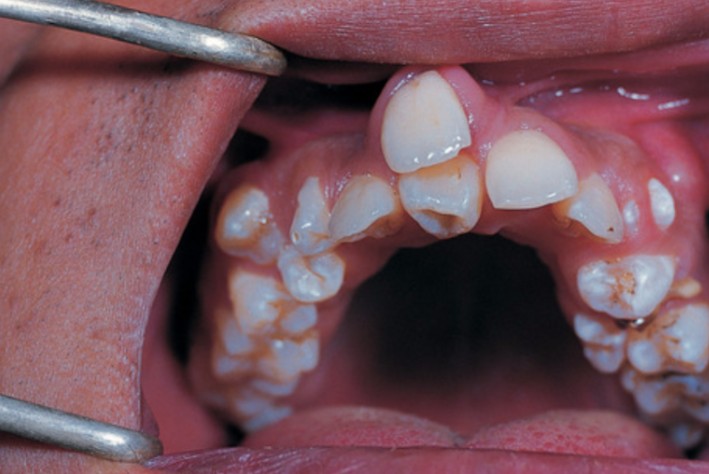

來自湖北武漢的黃女士最近非常擔心兒子,因為正在換牙的兒子竟長出了「雙排牙」。

黃女士的兒子「樂樂」今年8歲,他同學從6歲開始就陸續換牙了,他卻一直沒動靜,直到8歲後他才出現換牙的情形。由於舊的乳牙沒及時脫落,而下排牙齒中間長出的兩顆新牙,被擠在一起了,中間還有半顆牙的空隙,看上去就像長了雙排的異形牙。醫生看過後,說這是兒童常見的狀況,但是責任是在家長身上。

醫生表示雙排牙的孩童情形越來越多。